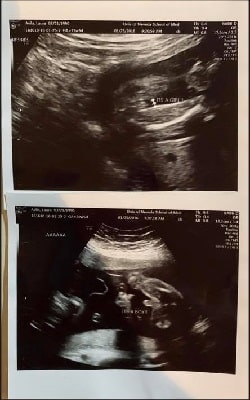

Ultrasound Photos at 23 Weeks Pregnant With Twins